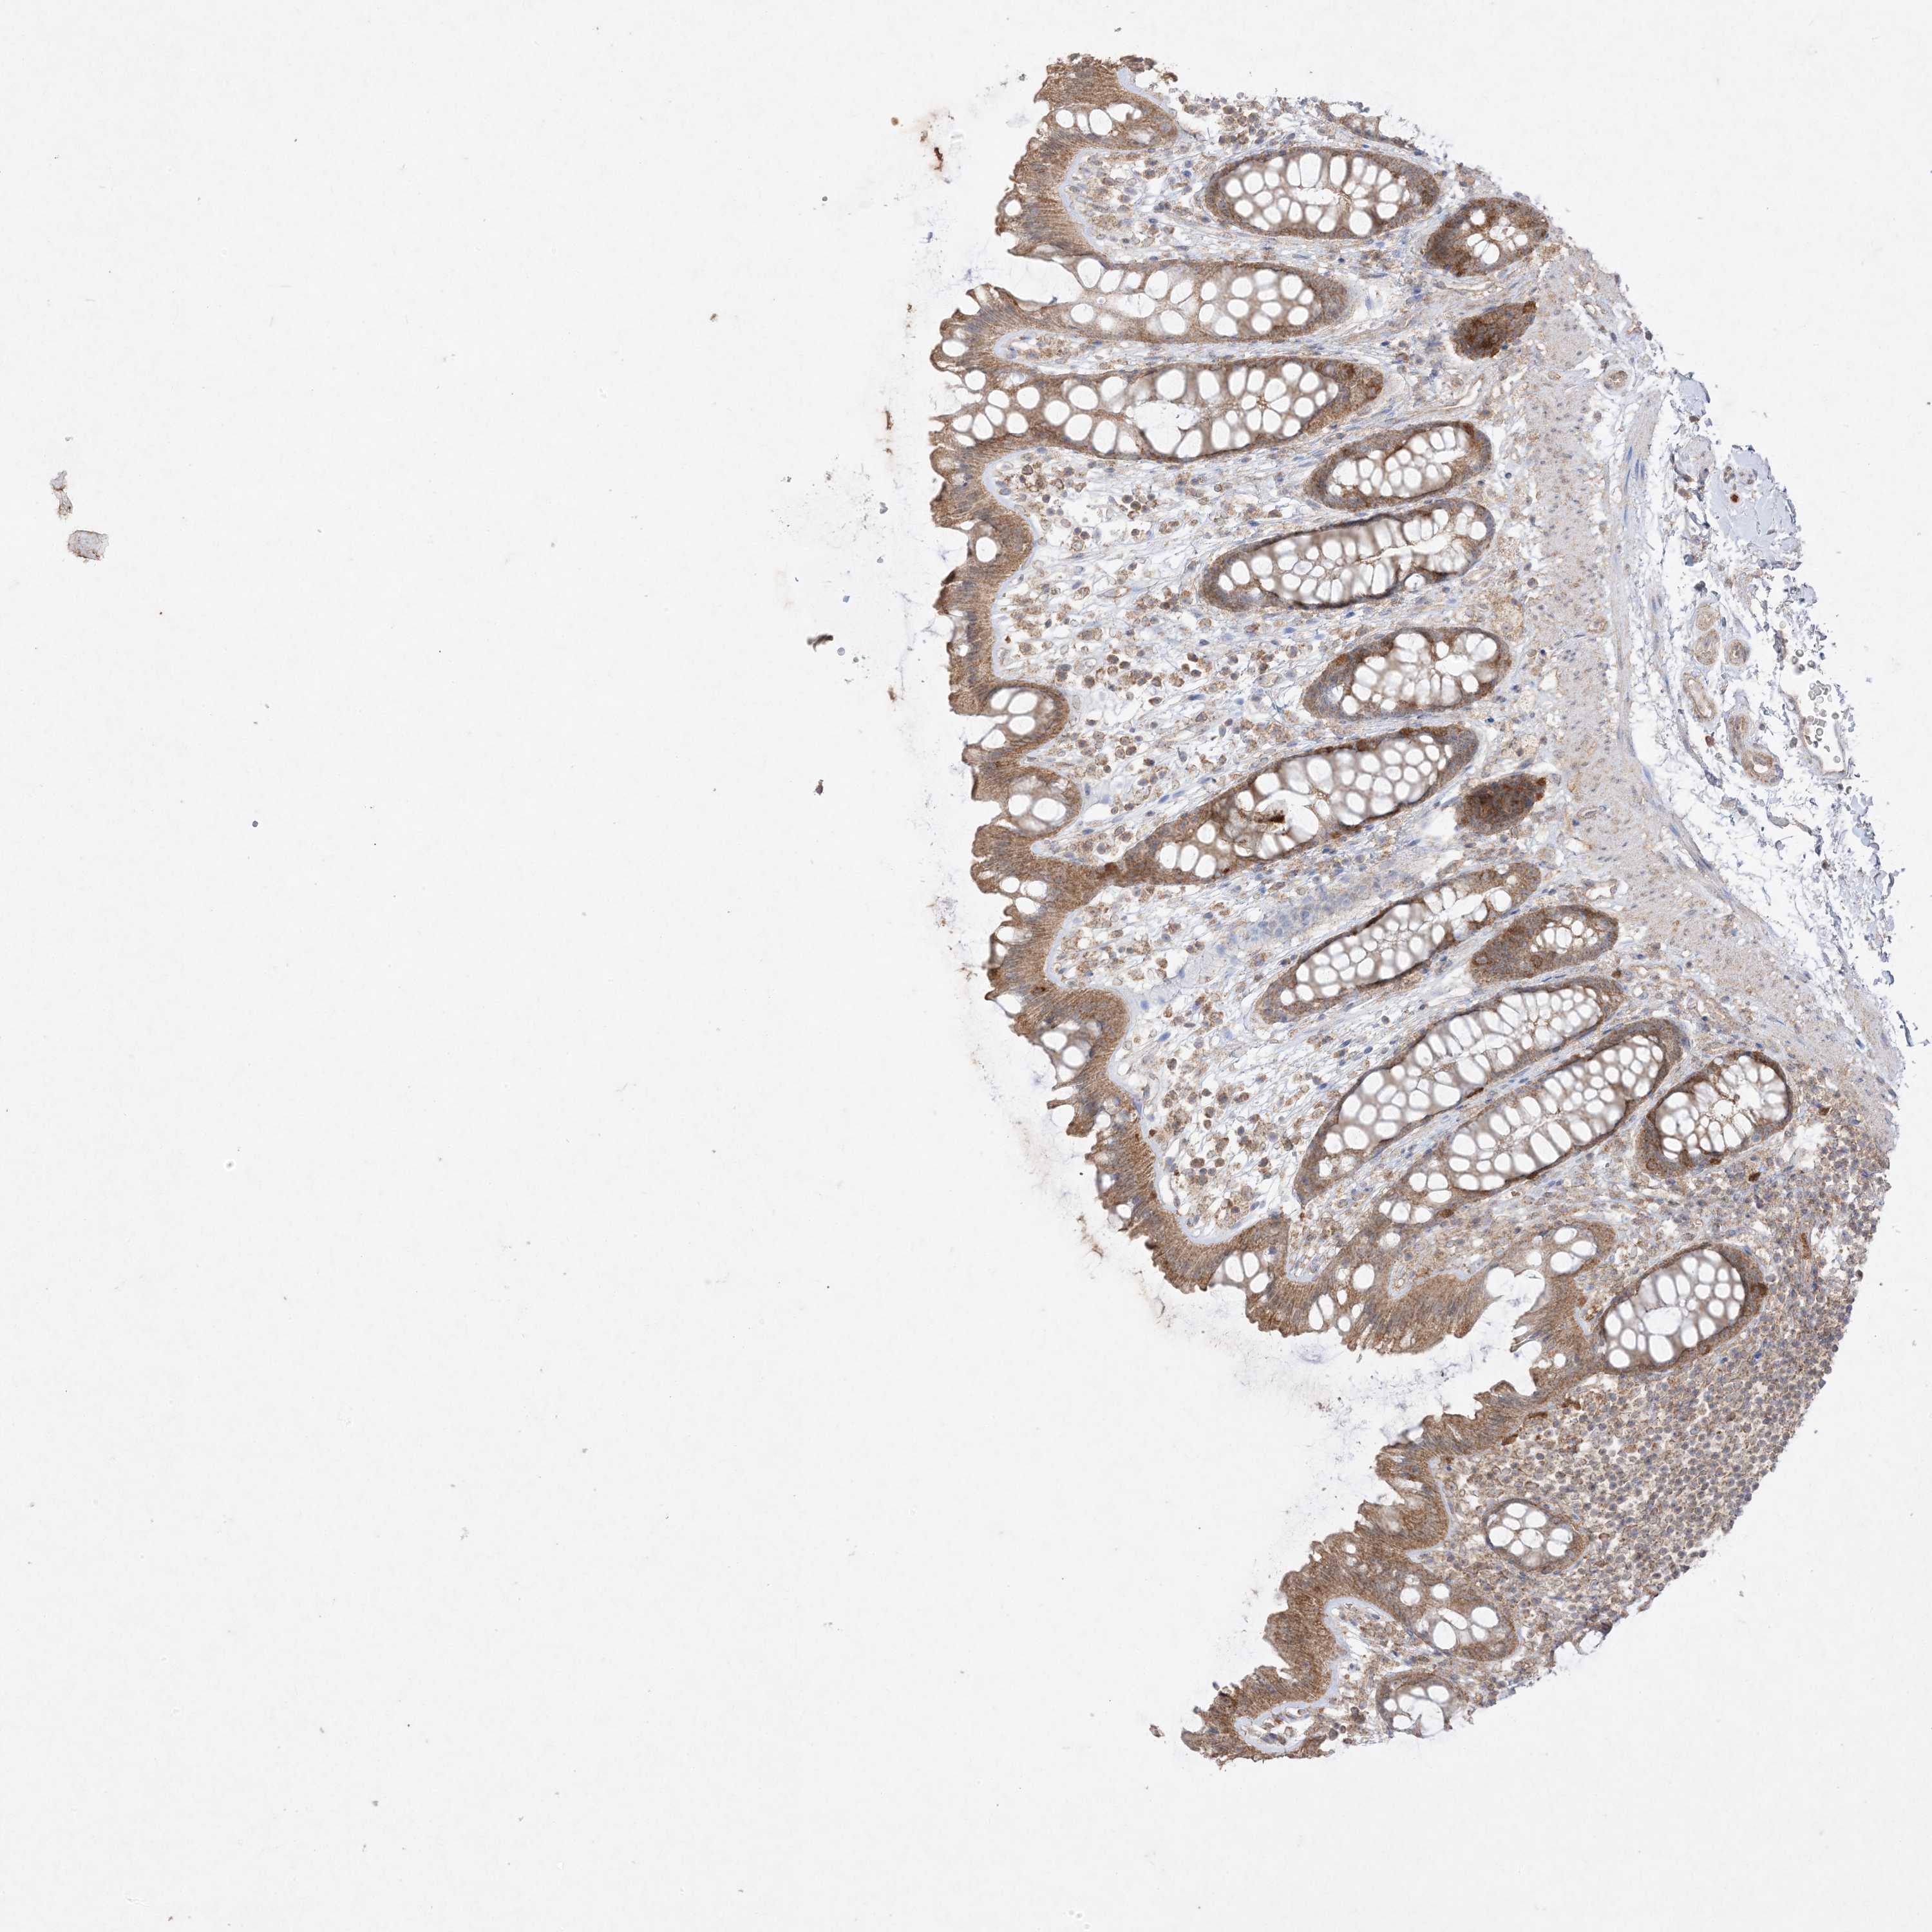

UBE2C